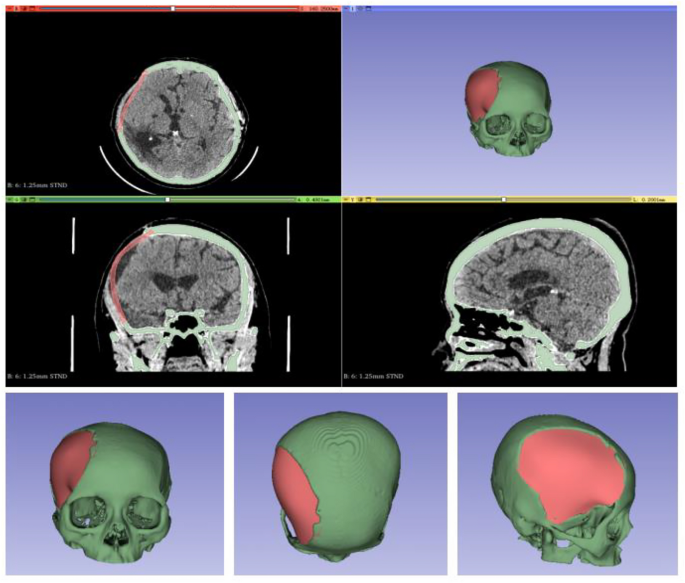

Initially, we acquired CT data of the patient’s head and imported the first postoperative CT image into computer software. The region of design for 3D head reconstruction was designated (Fig. 1). Along with the location, size, and shape of the skull resection, the shape and size of other parts of the head, as well as the thickness of the patient’s scalp, were considered. Based on scalp thickness measured during surgery and clinical experience, the original skull was expanded by 2 cm.Using the 3D Slicer image processing platform, the patient’s imaging data was processed and a 3D head model was digitally designed. The final model was saved in STL format. This file was imported into the 3D printing software (UltiMaker Cura), where model parameters, supports, and placement were adjusted. The model was then automatically sliced and sent to the 3D printer (CREALITY CR-M4, China). PLA (CREALITY) resin material was heated, melted, and extruded layer by layer. After printing, the model supports were removed, leaving the personalized head model (Fig. 2).

3D printed model of the patient’s head. Among them, the red is the skull defect of the patient.